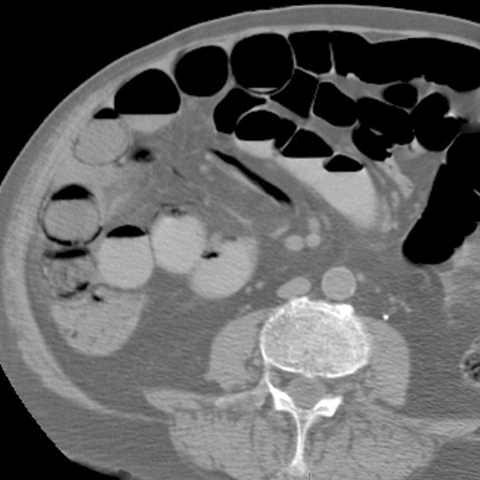

65 year-old male presents with a sudden onset of abdominal pain and bloody diarrhea. [2 of 2]